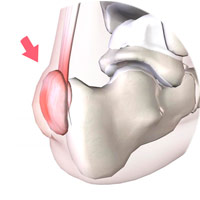

Síndrome de Haglund